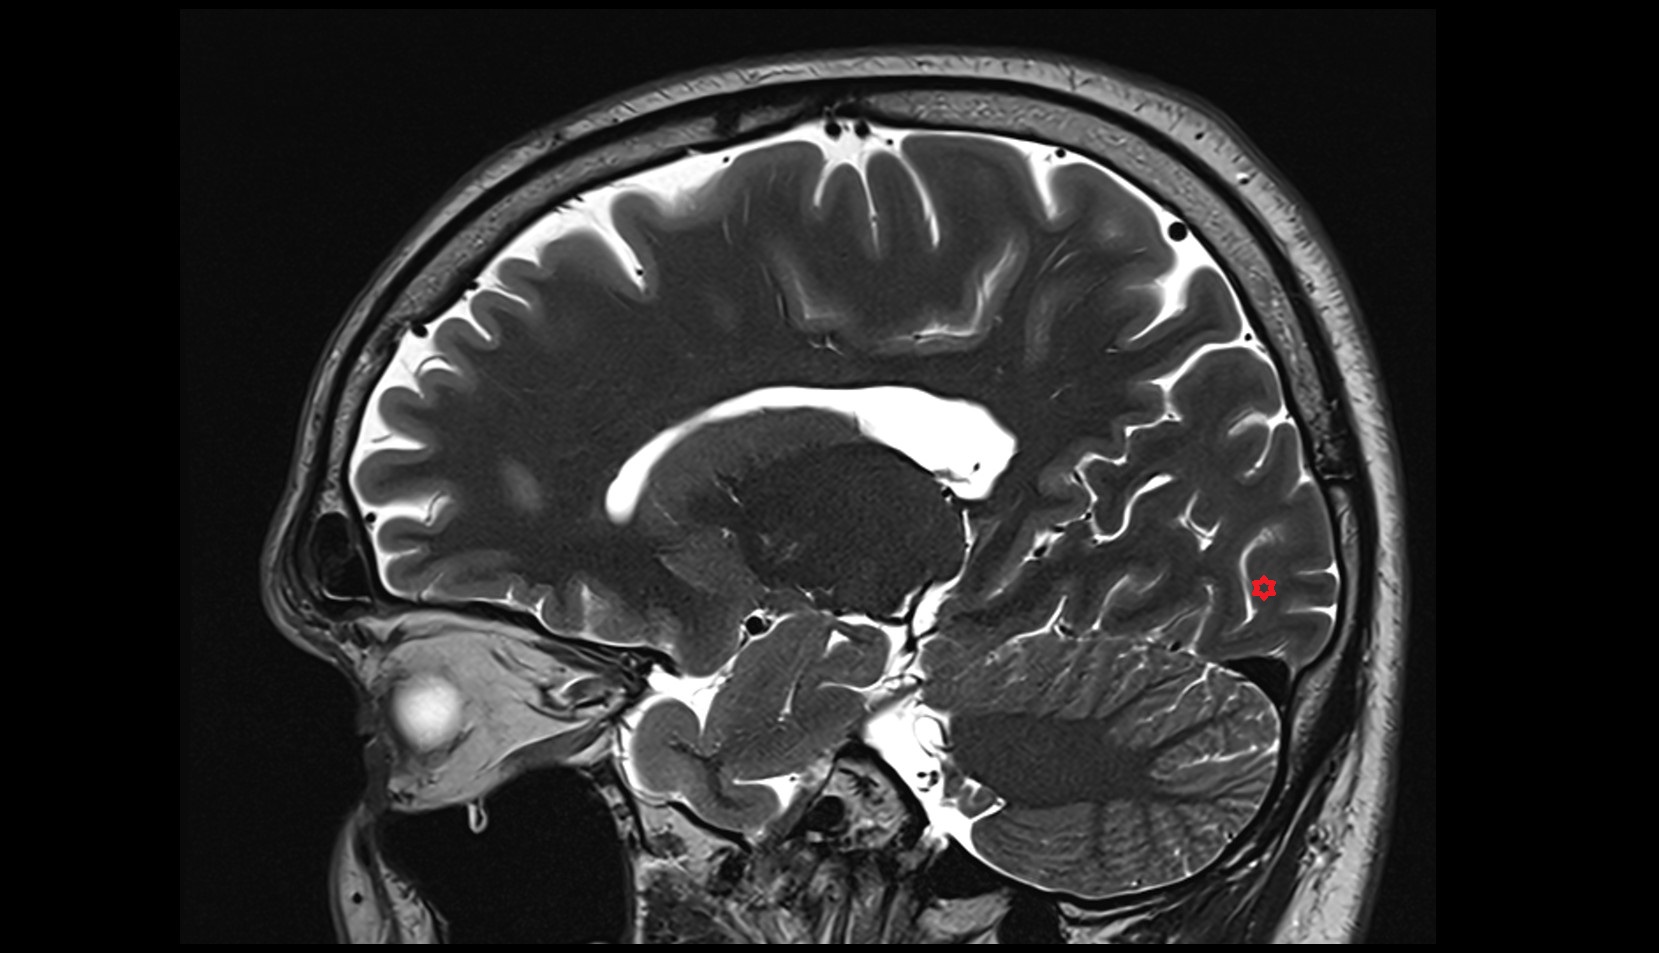

- Pineal gland